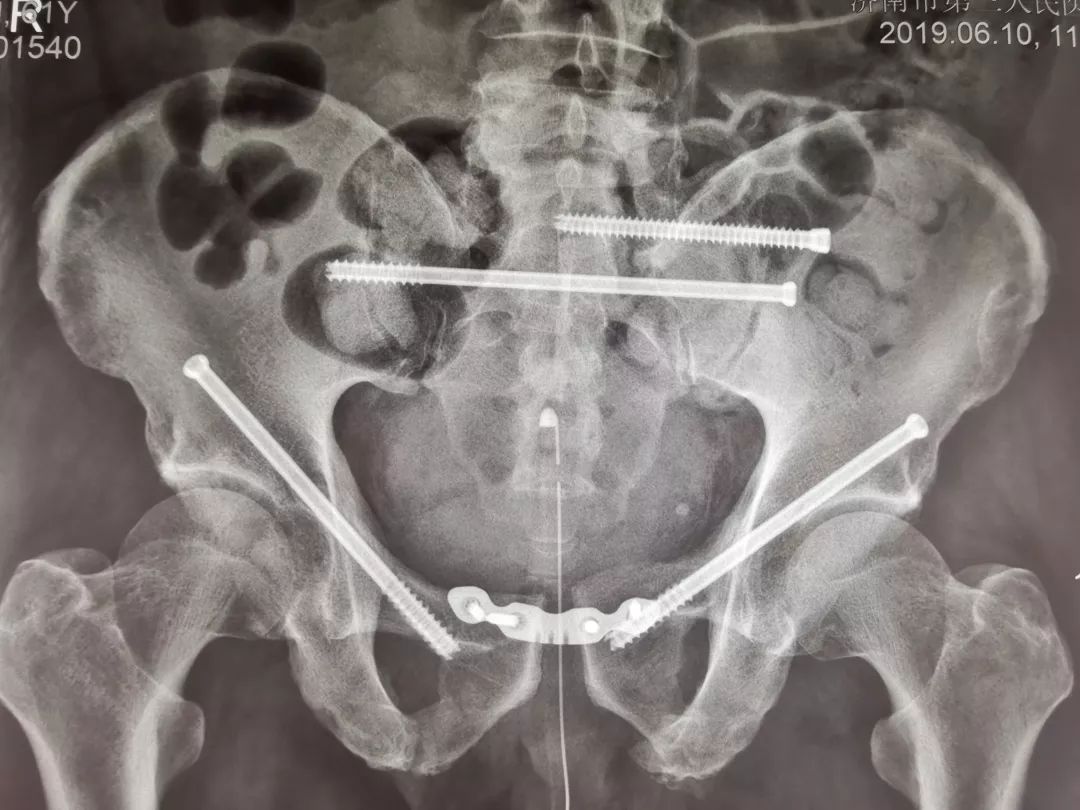

骨盆骨折病例展示 - 好大夫在线

图片尺寸3120x4160